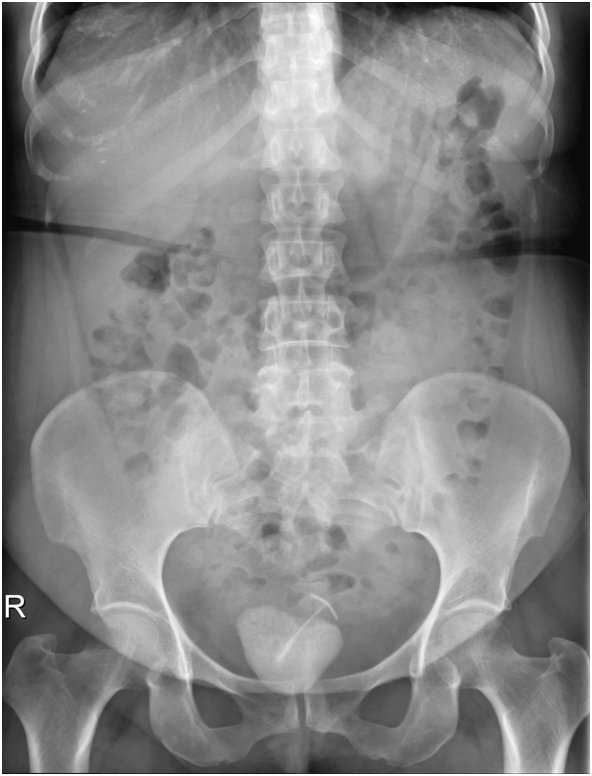

On initial evaluation with ultrasound (Figure 1) revealed a vesical calculus. On further evaluation with X-ray KUB (Figure 2) and CT Scan (Figure 3) (Figure 4) showed large laminated vesical calculus and Copper T seen outside the uterus with horizontal portion in the vesicouterine pouch, long vertical portion seen protruding into the urinary bladder lumen through the posterior wall partly encased in the vesical calculus.

Figure 1 Ultrasound.